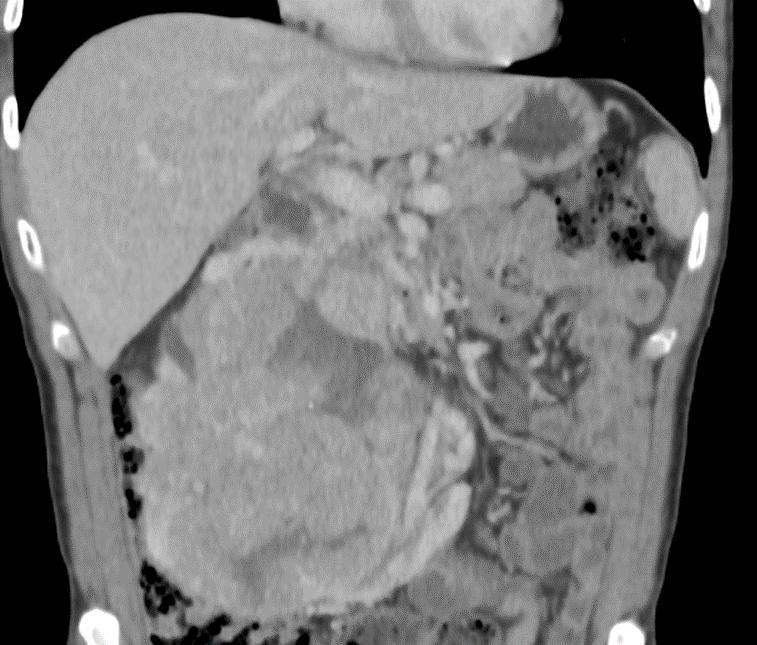

Kombinace systémové a chirurgické léčby u pacienta s primárně inoperabilním renálním karcinomem podkovovité ledviny: význam multioborové spolupráce – aktualizované výsledky 3letého sledování

Combination of systemic and surgical treatment in a patient with primarily inoperable renal cell carcinoma in a horseshoe kidney: the importance of multidisciplinary collaboration – updated results of 3-year follow-up

Jiří Herman, Vladimír Študent jr., Aleš Vidlář, Anežka Zemánková, Igor Hartmann